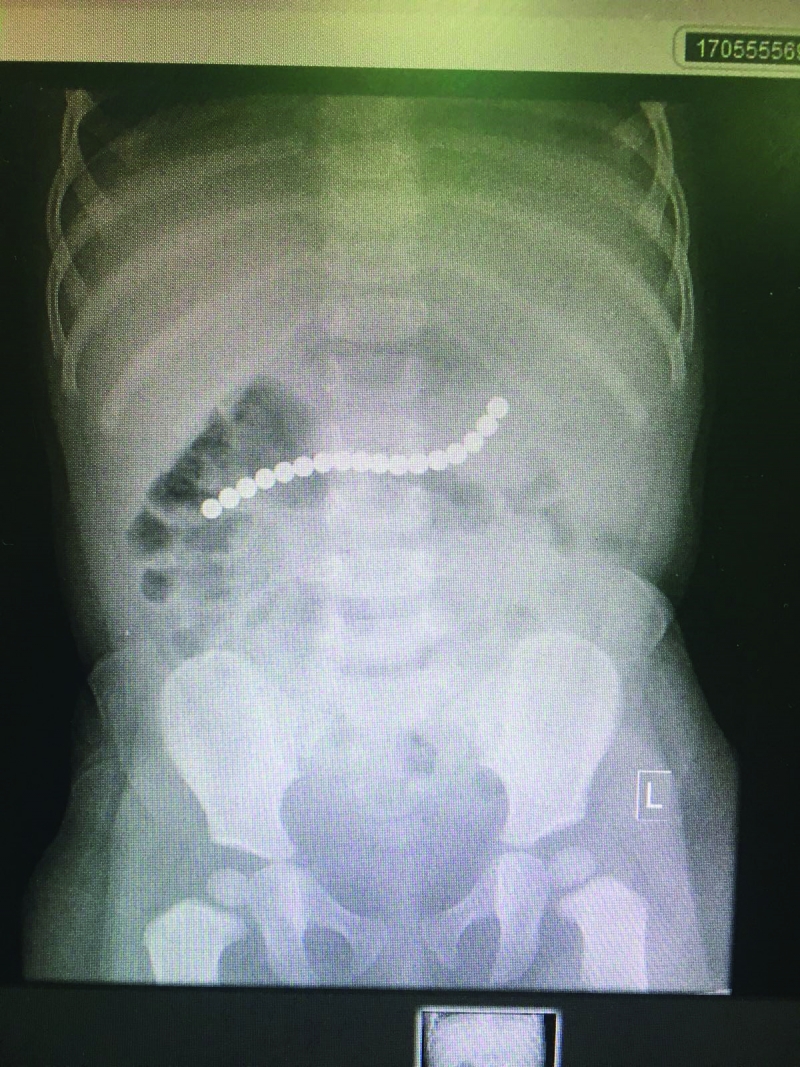

Magnetic beads removed from 14 months old girl’s stomach

A Bahraini child who swallowed magnetic beads has undergone a successful surgical operation at the Salmaniya Medical Complex (SMC).

A SMC medical team led by Consultant Pediatric Surgeon Dr Faiza Haider conducted the operation and removed the metallic objects from the girl’s stomach.

“An X-ray showed the presence of the magnetic beads in the 14-month girl’s stomach, which led the medical team to conduct the surgery and save her life,” said SMC Chief Surgeon Dr Rani Al Agha. The girl, who suffered continuous vomiting, was rushed by her family to the SMC emergency after her mother noticed that some magnetic beads were missing.